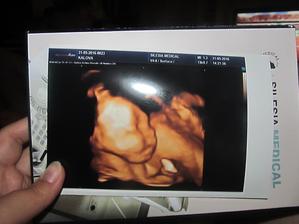

Klokan přiletí v září

jééé, krásný bobišek 😉 a už takový velký...